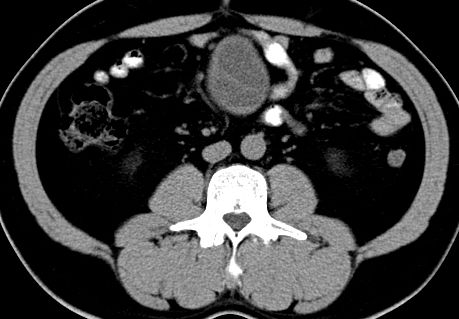

(腹腔)神经鞘瘤

男,48岁,间断性下腹不适1年。

手术探查

:距回盲部28厘米处肠系膜根部可见5*7cm左右包块,质中等硬度,活动度尚可,肝、胆、胰、脾肾未见明显异常。

病理

:(腹腔)

神经鞘瘤

,伴出血、坏死及囊性变,伴淋巴结反应性增生。

免疫组化结果

:sma(-), desmin(-), cd117(-), s-100(+++), nf(-),vimentin(+++).